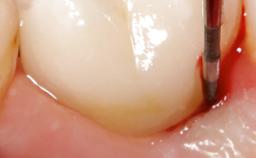

A 65-year-old female patient was referred to the periodontist for assessment and management of infection associated with an implant at site 12. The general dentist had noted suppuration on probing during examination.